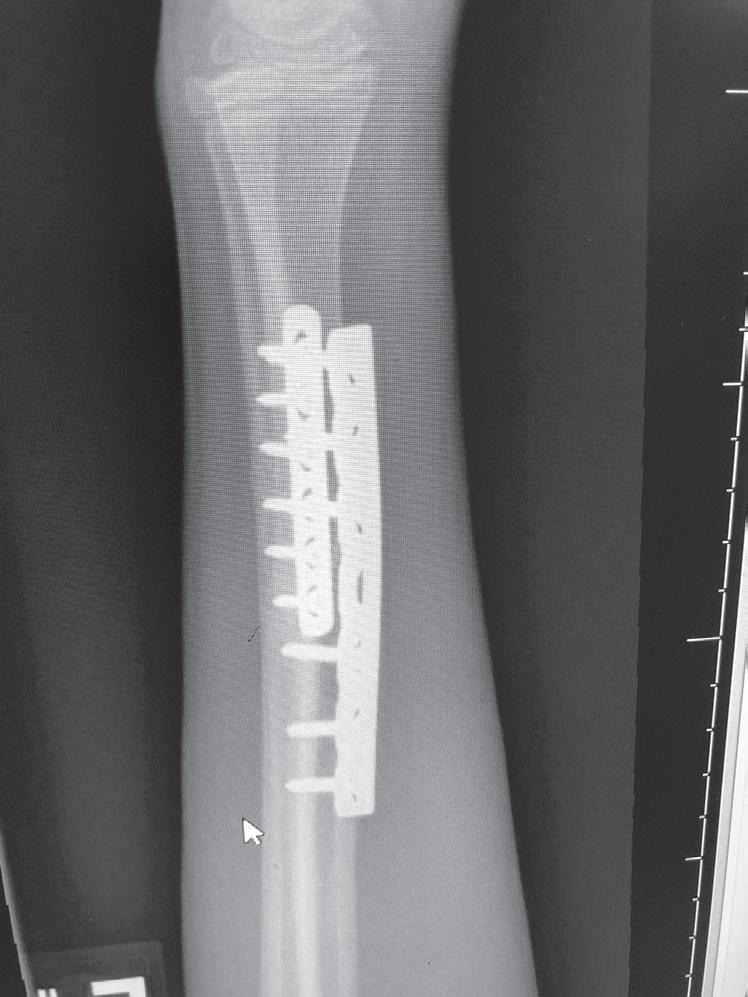

The remodeling of the metaphyseal region to create the trumpet shape can be an issue after plates and screws are placed in the metaphysis for fractures. Physeal growth results in the physis “growing away” from the plate, and the “cut-back” remodeling can result in long screws that are prominent medially (Fig. 1.10).74 In addition to this problem, lateral plates placed on the distal femur adjacent to the

AB

Fig. 1.10 Anteroposterior radiographs of 12-year old male who underwent open reduction and internal fixation of a supracondylar femur fracture at 1 month (A) and 18 months (B) postoperative. The significant growth of the distal femur resulted in physis “growing away” from the screws and the screws becoming prominent on the medial side.

physis that are left in growing patients can result in substantial valgus deformity.75,76